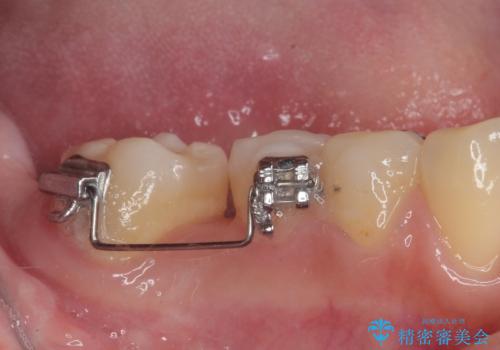

奥歯が1本欠損した状態で矯正治療を行っていたそうですが、どのように治療を終了させるか未決のまま矯正装置を除去してしまい、暫く放置されている状態でした。

理想的には残っている歯のスペースを詰め、最後方にインプラントを埋入することが理想的ではありますが、矯正治療期間や費用の面から、前後に歯を大きくする補綴治療を行うことで対応することとなりました。

矯正装置を長いこと付けていたことで、歯が大きく捻転してしまい、舌に当たる感覚を気にしていらっしゃいましたが、補綴治療により捻転とともに解消することができました。

上顎の最後臼歯と咬み合わせるために前後径が大きくなっており、歯肉周りに汚れが溜まりやすくなるため、日々の清掃と定期的なクリーニングが必要となります。